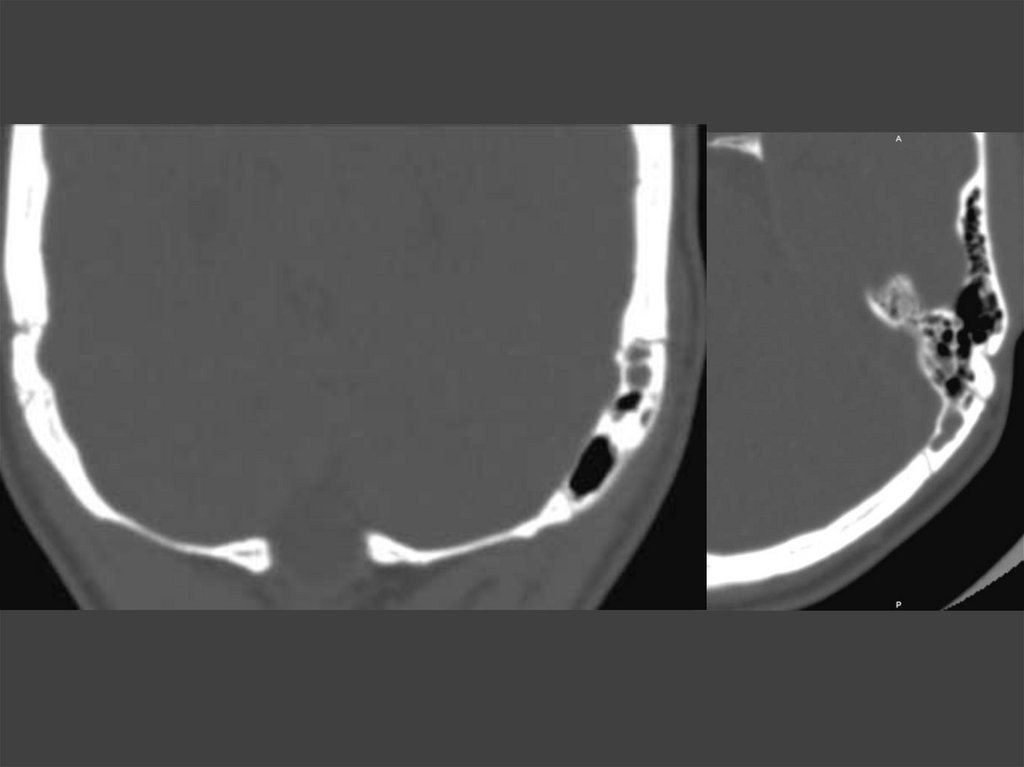

153. Стеноз НСП

152. Стеноз наружного слухового прохода

Пороки развития

Стеноз наружного слухового

прохода